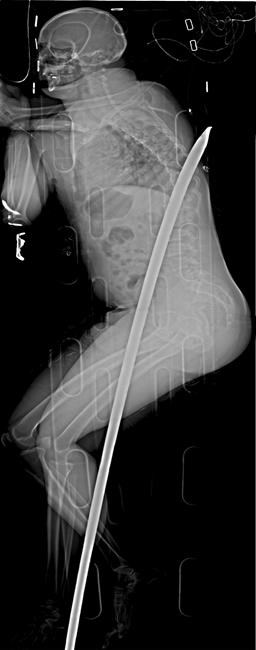

Daniel de Wet lost a kidney and suffered other internal injuries when the 1.8-meter (5.9-foot) metal rod entered his groin area and exited his back just below a shoulder blade.

De Wet’s horrific accident occurred in January 2015 when he slipped onto the crowbar in a mine in Carletonville, a gold-mining area near Johannesburg. He was conscious and sitting awkwardly on a stretcher with the crowbar in his torso as rescuers took him to the surface, where he was airlifted to a hospital. Trauma surgeons removed the crowbar and de Wet was discharged 19 days later.